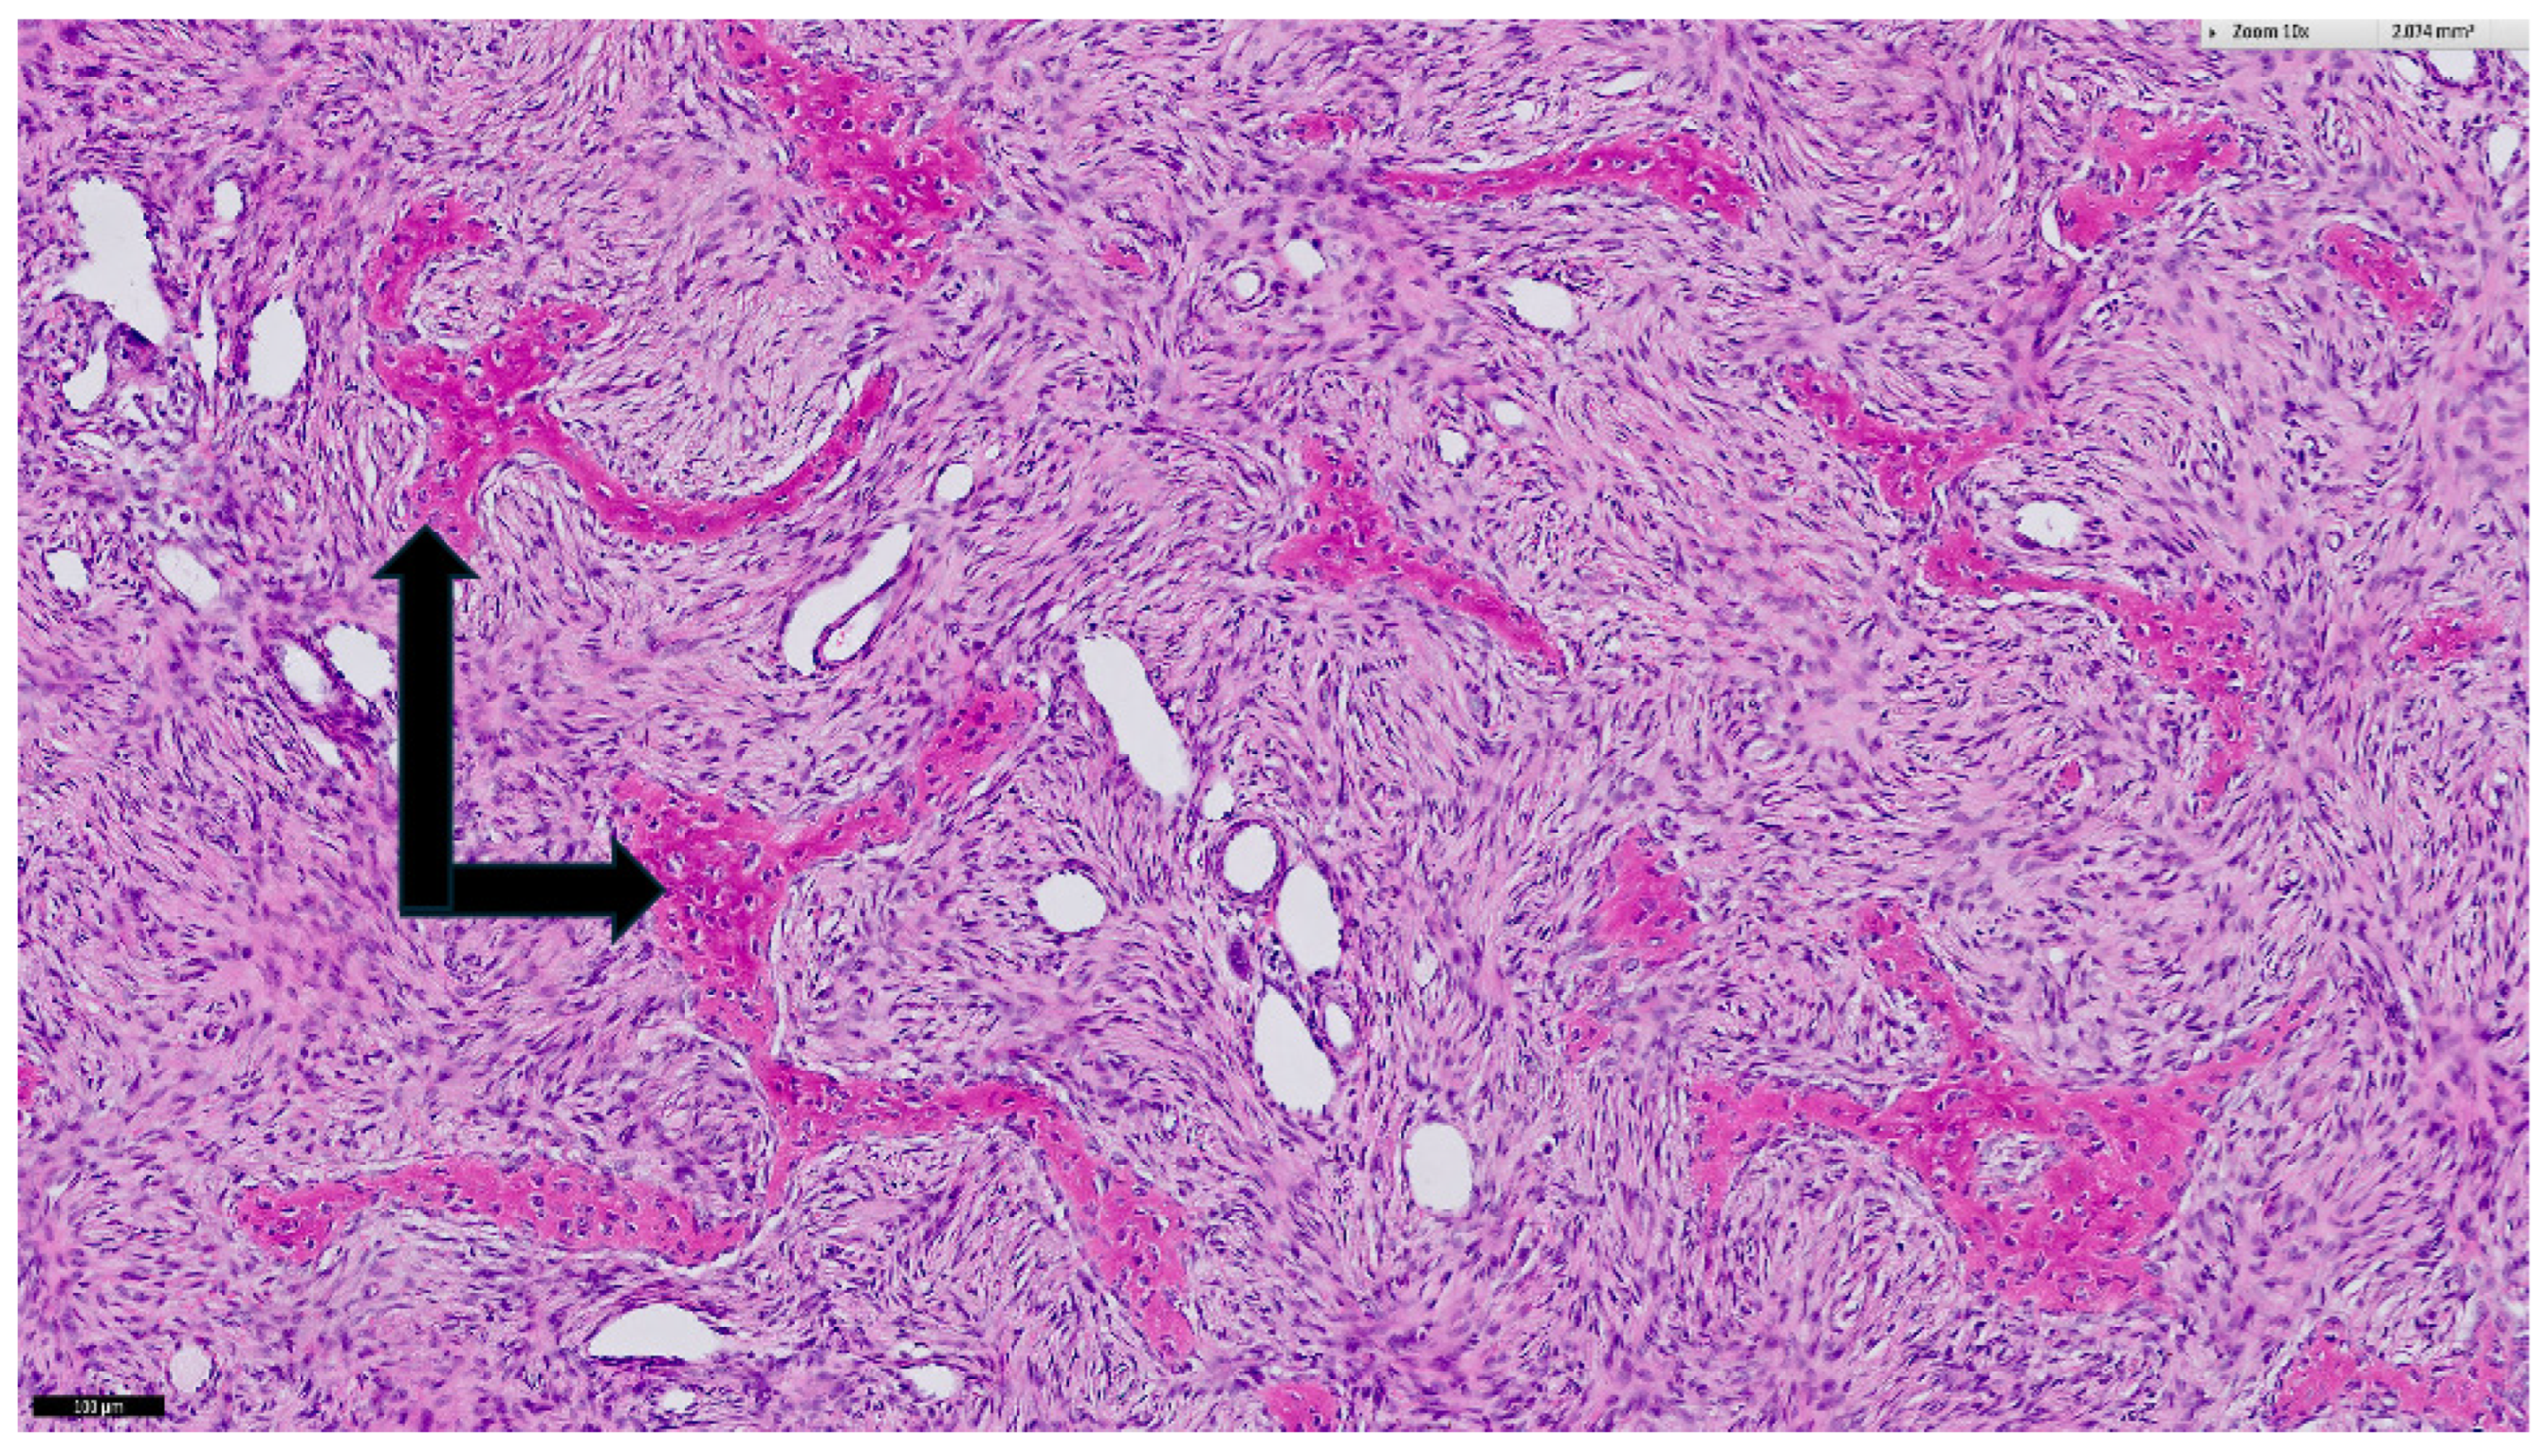

The dimensions of the resected tumor were 17 × 20 × 18 cm3 with a weight of 1949 g. Histology again showed the typical aspect of FD (Figure 6). The right middle lobe contained severe parenchymal hematoma and a deformed lobar bronchus. A lobectomy of the right middle lobe was thus performed. Both the right lower and upper lobe were inflated adequately. The pectoral muscle together with the overlying breast tissue were used for closure of the thoracic wall defect.

Figure 6. Histological specimen of the resected mass. Hematoxylin and eosin microscopy show the typical morphology of fibrous dysplasia of bone represented by spindle cell stroma harboring irregular trabeculae of woven bone (black arrows) with irradiating collagen fibers. The black bar in the lower left corner corresponds to 100 µm.